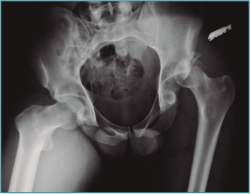

Se trata de un varón de 57 años que sufre luxación posterior de cadera izquierda con fractura conminuta de la ceja posterior del acetábulo tras un accidente de tráfico (Figura 3). Se trata mediante reducción cerrada de cadera dentro de las 6 primeras horas posteriores a la luxación. La reducción fue satisfactoria pero la TC muestra la presencia de fragmentos intraarticulares. Se le realizó tratamiento artroscópico de cadera con extracción de fragmentos.

Figura 3. Radiografía anteroposterior de pelvis donde se muestra la luxación posterior de la cadera izquierda.